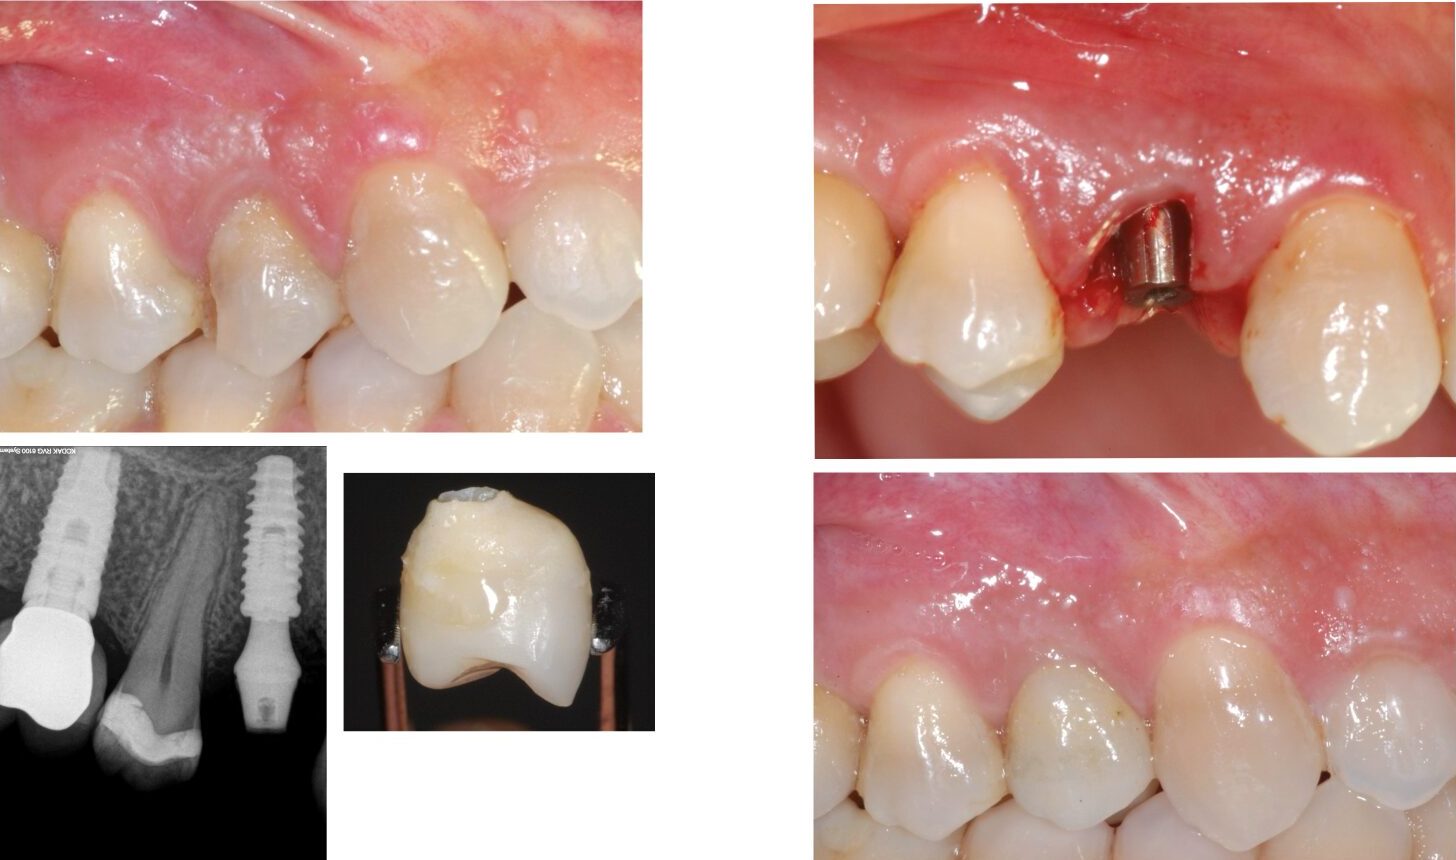

• TERAPIA IMPLANTARE DEI SETTORI ANTERIORI

• RUOLO DEL PLATFORM SWITCHING NELLA

ANALISI DEL RIASSORBIMENTO CRESTALE

• PROTOCOLLI CHIRURGICI NELL’ INSERIMENTO

DELL’ IMPIANTO POST ESTRATTIVO IMMEDIATO E

DIFFERITO A MEDIO E LUNGO TERMINE

• LE RIAPERTURE, GESTIONE DEI TESSUTI MOLLI, INNESTI DI TESSUTI MOLLI

• IL CARICO IMMEDIATO

• PROTESI SU IMPIANTI